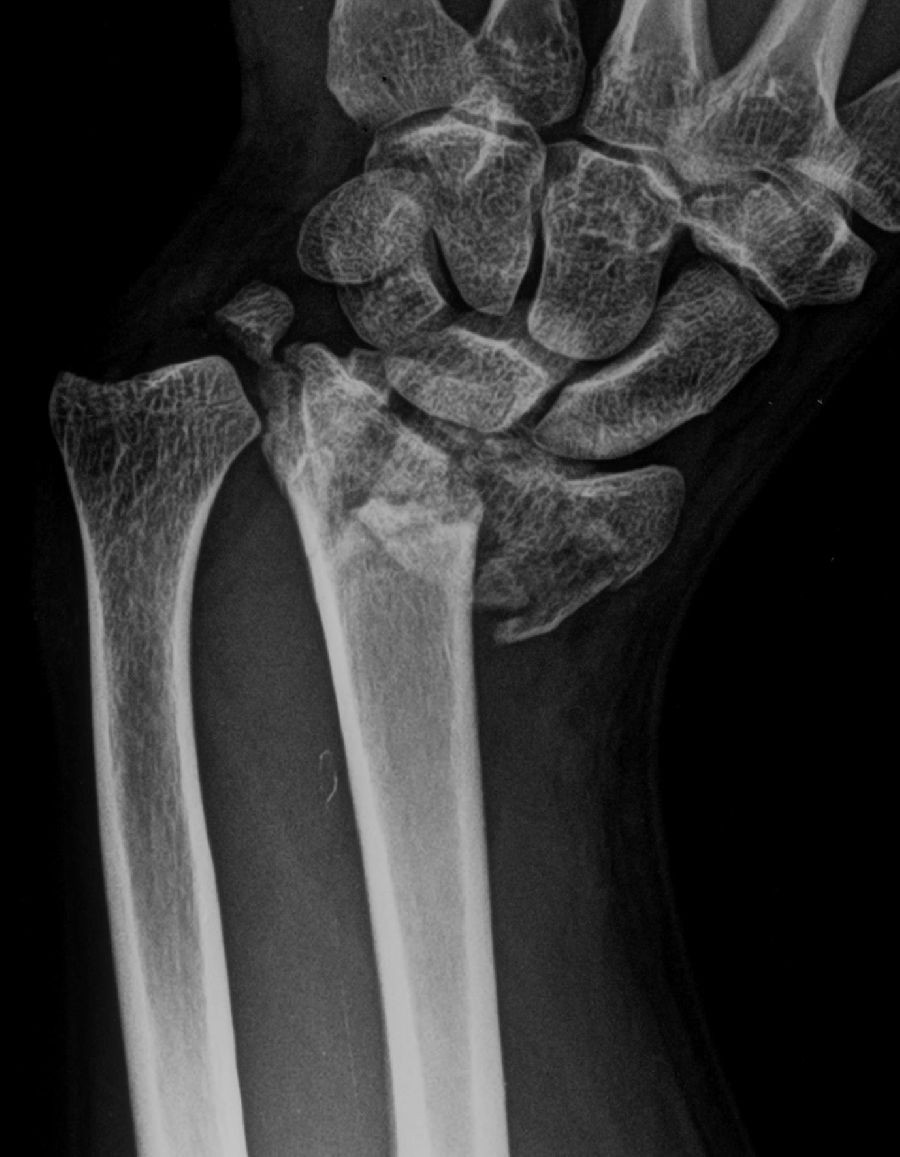

Investigadores del King`s College de Londres han desarrollado un material que permite el trasplante de células madre formadoras de hueso en fracturas óseas graves y acelera el proceso de curación. Este nuevo método mejora la reparación y puede cambiar la forma en que se tratan los huesos rotos, aseguran los autores del estudio, publicado en Nature Materials.

El artículo describe células madre y células óseas maduras cultivadas en un biomaterial, en una estructura que simula partes del hueso sano. El avance podría conseguir que haya menos complicaciones, infecciones y malos resultados en caso de lesiones graves.

El avance podría marcar una diferencia drástica en los tiempos de recuperación de los pacientes con fracturas óseas graves. El proceso de curación de una fractura grave puede ser lento o incluso fallar en pacientes vulnerables como los ancianos o aquellos con problemas de salud subyacentes.

Los métodos actuales para reparar el hueso son el uso de implantes sintéticos o tejido de un donante, donde se extrae hueso de otra parte del cuerpo, para reparar la fractura. Este método se basa en la propia capacidad del cuerpo para curarse, que puede debilitarse después de una lesión grave.

Hasta ahora, las terapias basadas en células, en las que se cultivan células adicionales y se introducen en la fractura, parecen prometedoras. Sin embargo, las células implantadas en las tecnologías existentes a menudo mueren y carecen de apoyo a largo plazo para la curación del hueso.